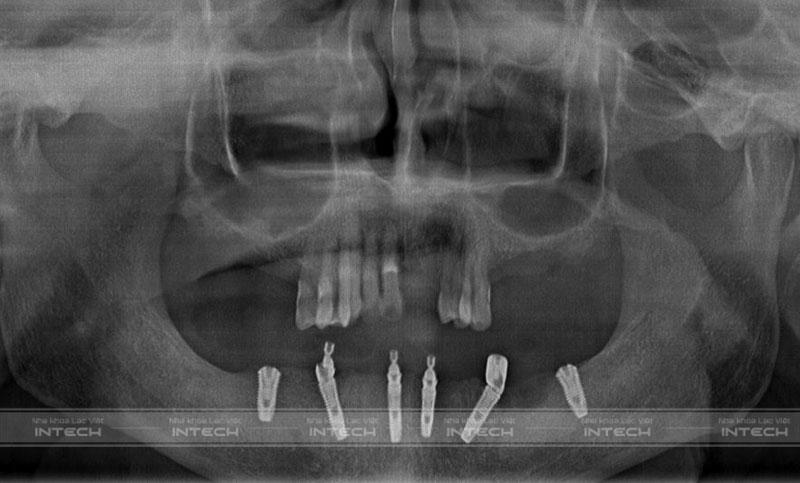

Hình ảnh phim chụp X-quang của chú Quản Văn Nghiệp sau cấy ghép Implant All-on-6 toàn hàm dướiHình ảnh phim chụp X-quang của chú Quản Văn Nghiệp sau cấy ghép Implant All-on-6 toàn hàm dưới

Qua thăm khám và chụp phim X-quang, đội ngũ bác sĩ tại Nha khoa Lạc Việt Intech đánh giá tình trạng của chú Nghiệp:

• Mất nhiều răng cửa hàm trên, các răng còn lại bị lung lay.

• Mất toàn bộ răng hàm dưới, khuôn mặt bị móm

• Ảnh hưởng tới tính thẩm mỹ, chức năng ăn nhai kém, gần như không thể cắn xé được.

• Trồng răng Implant toàn hàm All-on-6 hàm dưới

• Trồng răng đơn lẻ các răng đã mất ở hàm trên